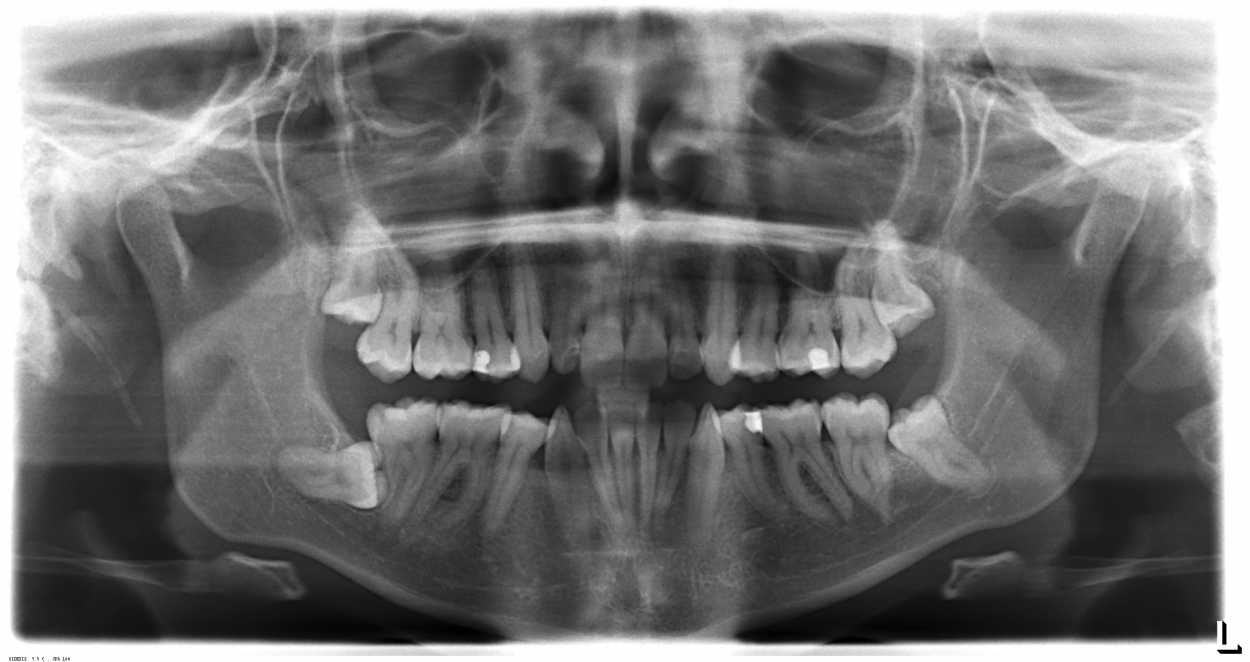

Buonasera, sono una ragazza di 26 anni e ho tutti i denti del giudizio inclusi. Non mi danno alcun fastidio, ma circa tre anni fa ho notato una piccola apertura della gengiva sopra il dente del giudizio inferiore sinistro. Il dentista mi disse di tenerlo pulito e di non preoccuparmi poiché, anche in base alle lastre fatte successivamente, il dente non spingeva e non dava problemi. Un paio di mesi fa ho notato che il piccolo buco nella gengiva si è un po’ allargato, ho quindi deciso di fare un controllo da un altro dentista, che mi ha fatto fare una tac. Dalla tac è risultato che la radice del dente del giudizio attraversa il nervo alveolare inferiore e toglierlo comporterebbe circa il 20% di rischio di perdita della sensibilità alla guancia e al labbro. Da un lato so che sarebbe meglio prevenire perché potrebbe causarmi infezioni, ma sto male al solo pensiero, da quando mi hanno dato questa notizia ho iniziato ad avere bruciore di stomaco e ad avere difficoltà a dormire (ho sempre avuto la fobia del dentista e ho brutti ricordi di estrazioni fatte in passato per mancanza di spazio). Nel caso decidessi non fare nulla sarei una pazza? E se in futuro mi si cariasse il dente adiacente, dovrei toglierli entrambi?

P.s. Le allego la panoramica fatta a marzo! Grazie ancora!

Ciao Alice. Innanzi tutto il primo consiglio che ti do é di non farti venire un’ulcera per la preoccupazione….Passando poi alla questione, non si puó nascondere che i tuoi denti del giudizio siano in una posizione anatomica infelice (sopratutto quello alla destra guardando la radiografia).

potrebbe gentilmente darmi un suo parere riguardo al mio dente incluso (in basso a sx nella radiografia)  ?

Ho effettuato una panoramica il 31.3.2017. In verità è almeno un anno che ogni tanto mi tira un po’ la corda del collo all’altezza dell’orecchio, non saprei dire, non è dolore, ma un fastidio che ogni tanto sento.  Pare quasi che sia un fastidio correlato alla mascella. La gengiva è normale, non arrossata, il dente non si vede e non si sente al tatto. Mangio normalmente senza dolore però quando apro molto la bocca mi sento un po’ che tira la corda del collo dalla parte dove c’è questo dente incluso. Mi sto chiedendo se ci sia magari un ascesso in corso? Non ho febbre ne nulla solo mi sto un po’ preoccupando che sia da togliere, considerando che i denti sotto possono dare problemi se si tocca i nervi della mandibola, ecc. Io non lo toccherei mai ma lei cosa pensa dalla panoramica allegata? Non penso ci sia nessun ascesso in corso o vede qualcosa di strano? Comunque se fosse da togliere dovrei rivolgermi a un normale dentista oppure no? Sarebbe facile da togliere oppure può essere che sia posizionato su qualche nervo della mandibola?

Ho evidenziato con le frecce i possibili problemi di quell’area. Il dente del giudizio incluso presenta un’area sospetta, che si crea se si apre uno spazio anche molto piccolo nella gengiva adiacente (freccia rossa). Ma anche il dente vicino ha un processo infiammatorio all’apice della radice. Ora dirle con certezza se i sintomi che ha siano correlati con questi fattori, non è possibile, ma se mi chiedesse cosa fare, avrei iniziato da qui.

Il dente del giudizio è molto vicino al nervo, ma con una radiografia TAC e un buon dentista non dovrebbe avere alcun problema.